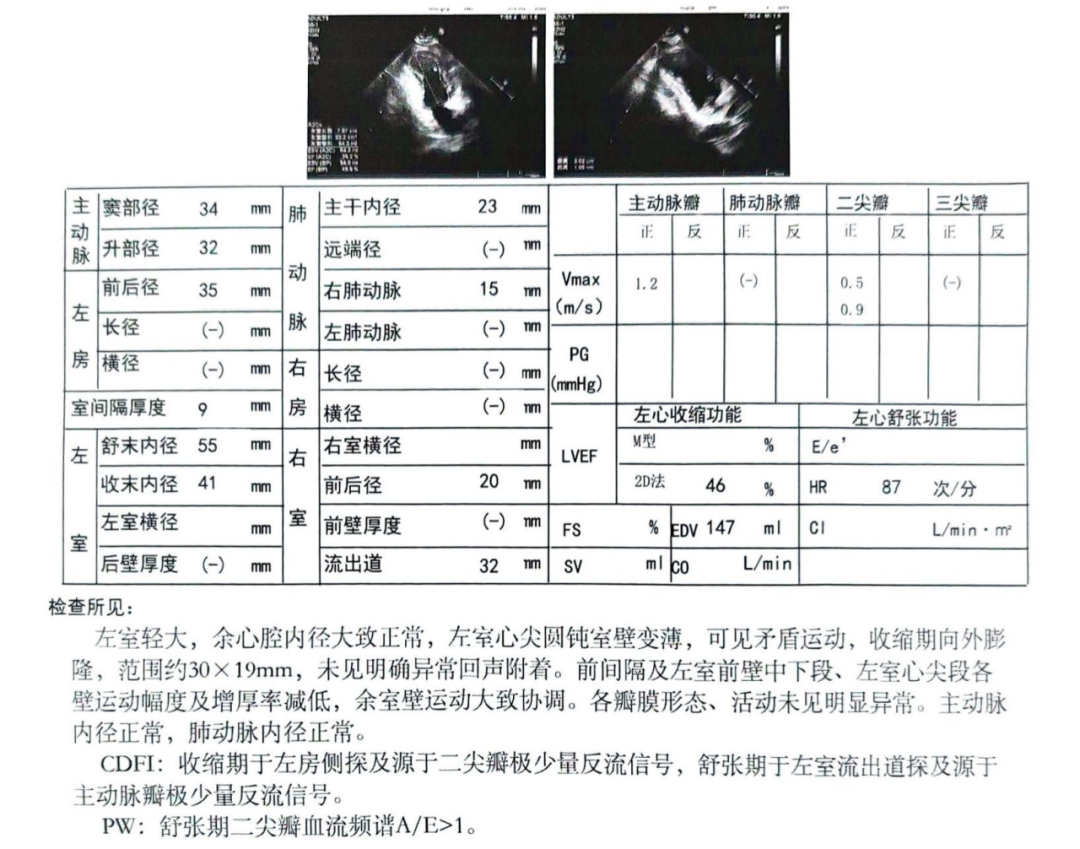

慢性疾病多 心肌功能差